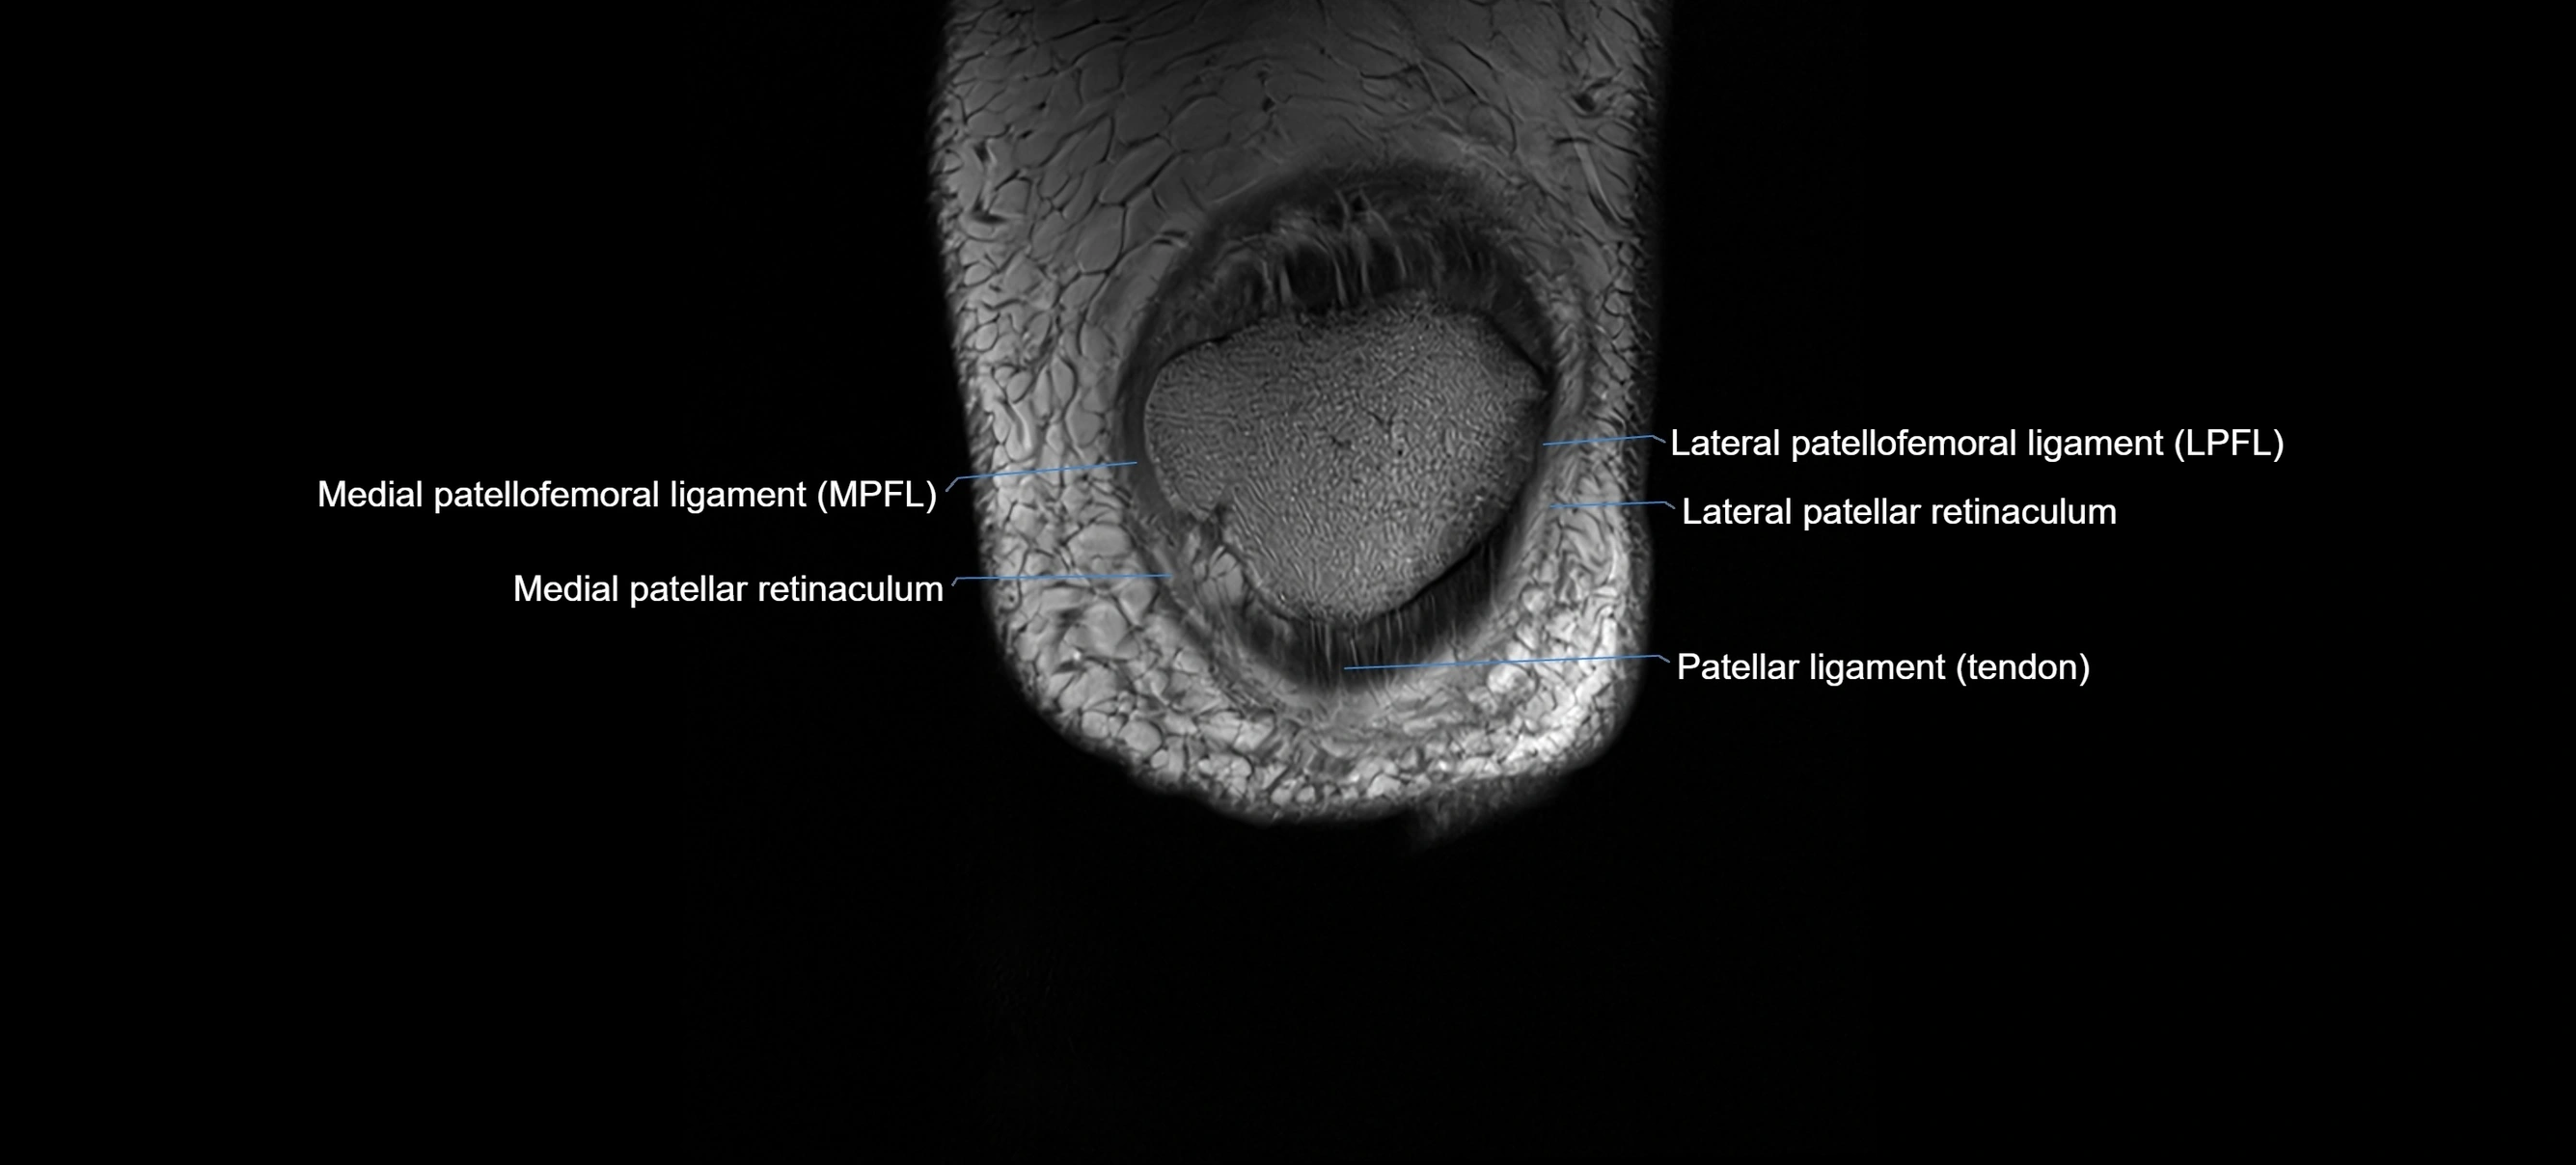

MRI images

image